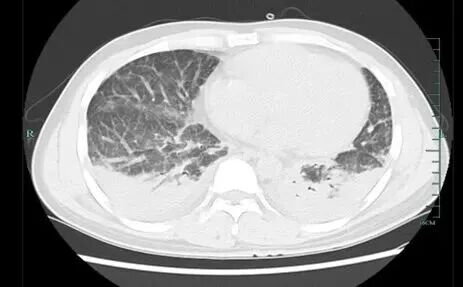

壮哥经检查:胸部CT双肺弥漫性病灶,血氧饱和度指标不到70%。“重症肺炎海通富配资,I型呼吸衰竭。再拖下去有生命危险!”他随即被安排住院治疗,并做了基因检测,揪出了真凶——马尔尼菲篮状菌。

壮哥的肺部情况